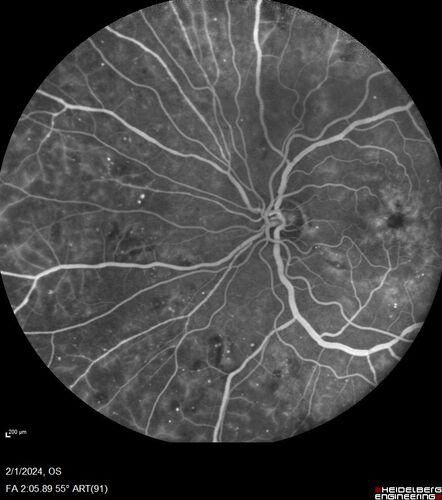

71 year old female with 3 months of vision loss and not feeling well.  She has been bruising on her legs.  Her vision was 20/100 in each eye with macular edema.  She was treated with Avastin and her CBC was checked.  She had a WBC of 267 thousand and was diagnosed with CML.

leukemia_118545_18.jpg leukemia_118545_19.jpg leukemia_118545_20.jpg leukemia_118545_21.jpg leukemia_118545_22.jpg